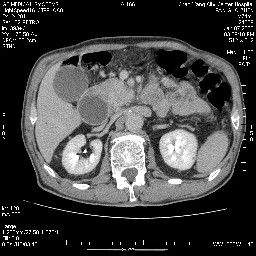

考虑来源于十二指肠水平段的恶性占位,侵及周围组织,特别是胰腺,可见区域淋巴结肿大,左侧下腔静脉畸形。

考虑来源于十二指肠水平段的恶性占位,侵及周围组织,特别是胰腺,可见区域淋巴结肿大,左侧下腔静脉畸形。支持

十二指肠水平段腔内占位伴梗阻,中等度较为均匀的强化,洗脱慢,区域淋巴结显示增多,符合腺癌表现。下腔静脉变异。

支持十二指肠腺癌伴梗阻.,下腔静脉发育变异.

十二指肠水平部腺癌伴梗阻并侵犯邻近结构。下腔静脉发育变异。